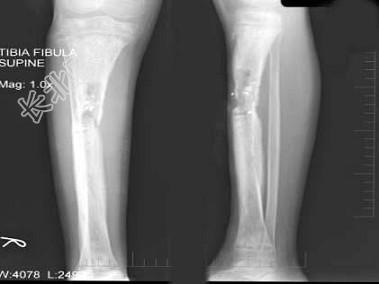

- 单项选择题女,12岁, 右小腿肿胀,疼痛, 发热3月余,摄片如图所示, 下列征象哪项是错误的 ( )

A、骨质呈溶骨性破坏

B、骨质增生硬化

C、骨膜呈层状增生不明显

D、可见软组织肿块

E、软组织肿胀